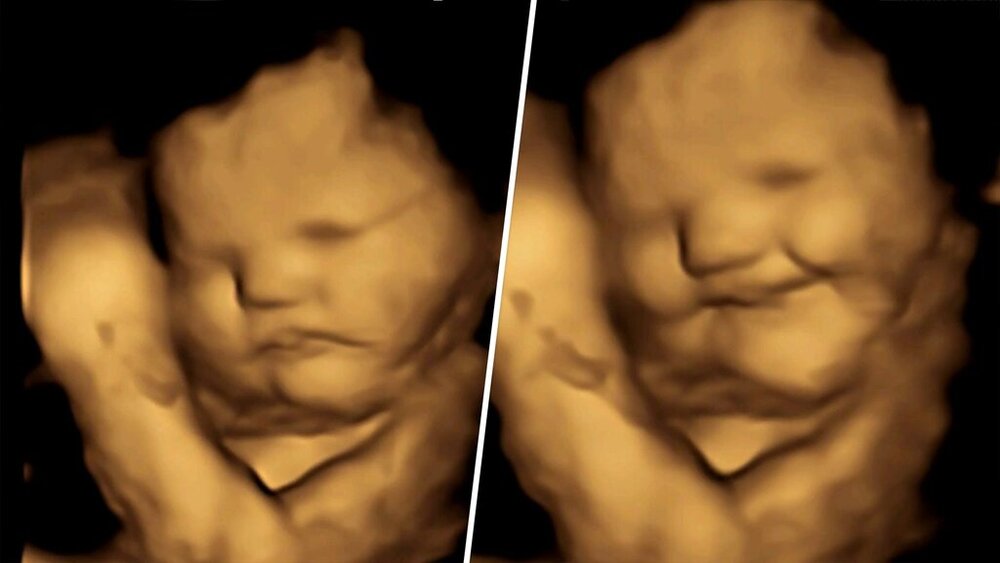

محققان شواهد خوبی مبنی بر اینکه جنین انسان به طعم و بوی خوراکی‌ها در رحم واکنش نشان می‌دهد پیدا کرده‌اند.

بر اساس یک مطالعه جدید که در نشریه معتبر سایکولوجیکال ساینس منتشر شده، فرزند به دنیا نیامده (!) شما در دوران رحمی حس بویایی و چشایی دارد و به نظر می‌رسد که جنین‌های انسانی می‌توانند به تفاوت طعم و عطر خوراکی‌ها واکنش نشان دهند.

در این مطالعه، محققان به ۱۰۰ زن باردار یک کپسول حاوی تقریباً ۴۰۰ میلی‌گرم هویج و یا پودر کلم پیچ دادند و از آنان خواستند تا حدود یک ساعت قبل از سونوگرافی ۴ بعدی، هیچ غذا یا نوشیدنی طعم‌دار دیگری مصرف نکنند.

۲۰ دقیقه پس از اینکه مادران کپسول هویج یا کلم پیچ را خوردند، محققان آزمایشگاه تحقیقات جنین و نوزاد دانشگاه دورهام در بریتانیا کار تصویربرداری را شروع کردند و در کمال تعجب با واکنش و میمیک‌هایی دیدنی از صورت جنین‌ها روبرو شدند.

جنین‌هایی که مادرانشان کپسول هویج خورده بودند، واکنش‌های خنده بیشتری نشان دادند، در حالی که آنهایی که طعم کلم پیچ را چشیدند، واکنش‌هایی شبیه به گریه نشان دادند.

واکنش‌های صورت این بچه‌های بانمک با گروه کنترلی که در معرض هیچ کدام از طعم‌ها قرار نگرفتند مقایسه شد.